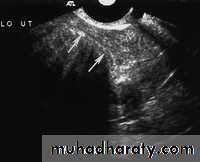

Rupture of hemorrhagic ovarian cyst:

Transabdominal scanned image

• Rupture of hemorrhagic ovarian cyst:

Transvaginal scanned image